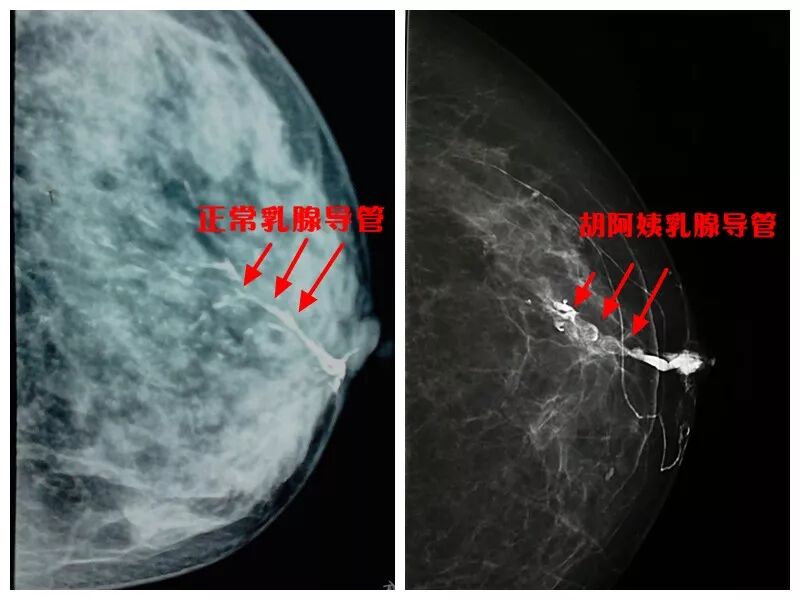

刘娜医生为她开具了乳腺B超、乳腺钼钯等检查。胡阿姨先做了乳腺B超,诊断结果仅为乳腺导管扩张,未见占位性病变。

钼钯图像也没发现有什么异常。但仝淑丽医生通过详细询问病史,还是捕捉到了一些病变的蛛丝马迹。

当天下午,刘医生和仝医生一同为胡阿姨做乳腺造影检查。她们经过耐心细致的对比,从众多非常细小的乳腺导管中找到了溢液的导管,并成功注入造影剂。

在造影剂的帮助下,在钼钯成像上,很明显地看到乳腺主导管扩张和乳头后方多个不规则充盈缺损影。可明确诊断,胡阿姨的乳腺导管内存在多发占位病变,怀疑是乳头状瘤,不排除恶性的可能。

我院在全市率先开展的乳腺导管造影技术,可以为乳腺导管内细微及早期病变提供更清晰、更准确的诊断信息,大大降低了误诊漏诊率。